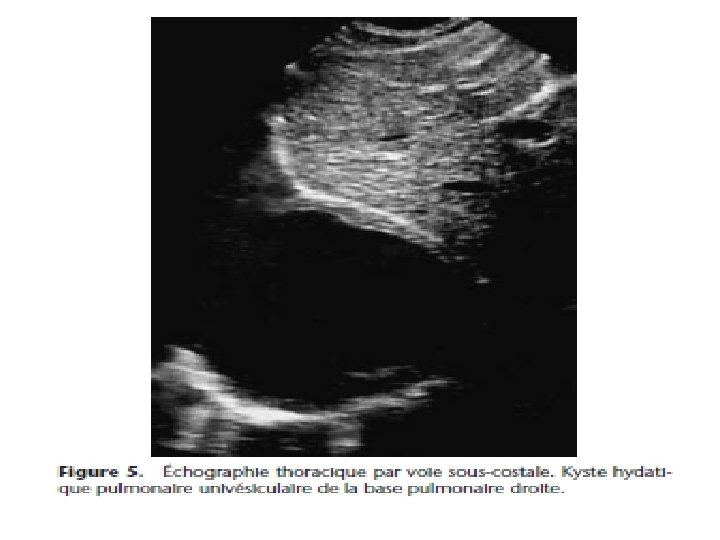

Kyste hydatique du poumon • Evolution radio-clinique 06 stades successifs: 1) Kyste sain. Asymptomatique de découverte fortuite (stade exclusivement radiologique)= opacité ronde, nettement limitée, en « boulet de canon » , dans un parenchyme sain, profil, opacité ovalaire « en ballon de rugby » , signe de NEMENOFF en radioscopie

Imagerie médicale